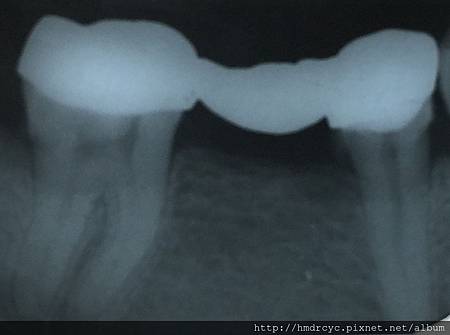

假牙必須利用X光片來更精確的判斷有沒有問題

在X光上面假牙是白色的影像

但X光片判讀困難 所以這部分必須仰賴醫師的專業

1. 蛀牙

蛀牙是常見的問題

臨床上可以在牙套邊緣勾到空隙

X光上則是一個黑色的蛀洞可以參考蛀牙範圍

X光通常會有1-2mm的誤差

所以實際上牙齒裡的洞會比影像大

只要牙套底下出現X光可以辨別的蛀洞

未來繼續蛀牙的速度會很快

牙套內的牙齒也會流失的很嚴重